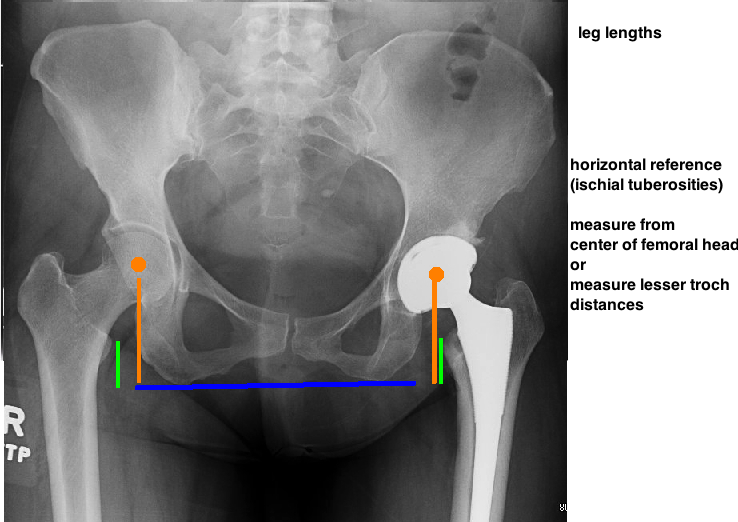

THEN EVALUATE STEM PLACEMENT.